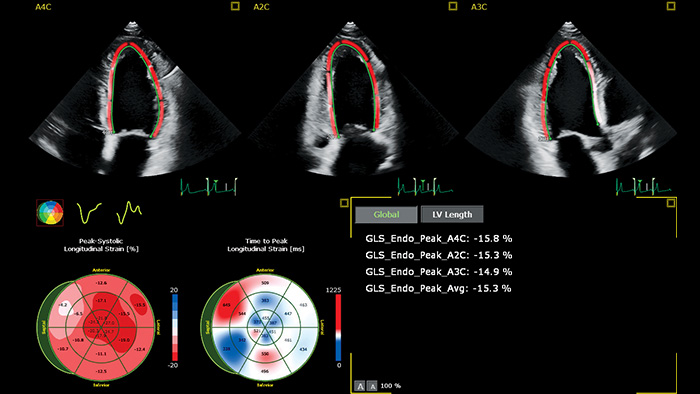

Toutefois, l'évaluation simple et largement disponible de la fraction d'éjection ventriculaire gauche (FEVG) par échochardiographie 2D ne permet souvent pas de détecter les petites modifications de la contractilité du VG. Des mesures plus précises sont disponibles en effectuant une FE volumique 3D. Mais c'est la déformation longitudinale globale (GLS) qui complète l'une ou l'autre analyse, en tant que paramètre de déformation longitudinale pour la détection précoce d'un dysfonctionnement subclinique du VG.4

Mesure automatisée des GLS pour un usage clinique en routine

Sur l'échographe ou pour le post-traitement, AutoStrain offre une solution GLS simple et rapide, pilotée par la reconnaissance automatique des vues et le placement automatique des contours. Un algorithme éprouvé sur plus de 6000 images pour assurer sa robustesse, AutoStrain VG fournit une mesure reproductible de la déformation du ventricule gauche par simple pression sur un bouton, pour une utilisation clinique quotidienne.